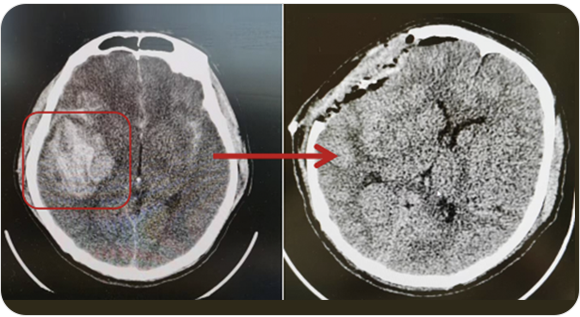

精通颅内动脉瘤介入栓塞和手术夹闭双技术,系统掌握脑动静脉畸形、颈内动脉海绵窦漏、硬脑膜动静脉漏等颅内血管疾病的诊疗和手术,精通颈动脉、椎动脉狭窄的血管内重建技术,以及颈动脉狭窄的内膜剥脱手术技术。在颅内肿瘤、椎管内肿瘤、颅脑损伤、高血压脑出血等疾病的诊治和手术,脑功能性疾病立体定向手术治疗等方面也积累了丰富的经验。